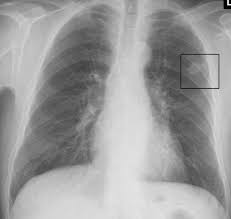

The most common cause of lung cancer is long-term exposure to tobacco smoke, which causes 80–90% of lung cancers. Nonsmokers account for 10–15% of lung cancer cases,  and these cases are often attributed to a combination of genetic factors, and exposure to; radon gas, asbestos, and air pollution including second-hand smoke. Lung cancer may be seen on chest radiographs and computed tomography(CT) scans. The diagnosis is confirmed by biopsy which is usually performed bybronchoscopy or CT-guidance. Treatment and long-term outcomes depend on the type of cancer, the stage (degree of spread), and the person's overall health, measured byperformance status. Common treatments include surgery, chemotherapy, and radiotherapy. NSCLC is sometimes treated with surgery, whereas SCLC usually responds better to chemotherapy and radiotherapy. Overall, 15% of people in the United States diagnosed with lung cancersurvive five years after the diagnosis. Outcomes are worse in the developing world. Worldwide, lung cancer is the most common cause of cancer-related death in men and women, and is responsible for 1.38 million deaths annually, as of 2008.